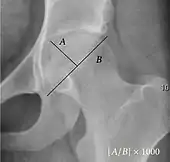

- Reimer's migration index (MI), also called the femoral extrusion index,[3] is calculated if hip dysplasia is detected. It can be used to indicate hip dislocation. It is the horizontal distance (parallel to the Hilgenreiner Line) between the Perkin line and the lateral border of the ossification center of the femoral head, divided by the horizontal width of the ossification center. The migration index is normally less than 33% by most sources,[9] but 25% and 30% has also been suggested.[10]